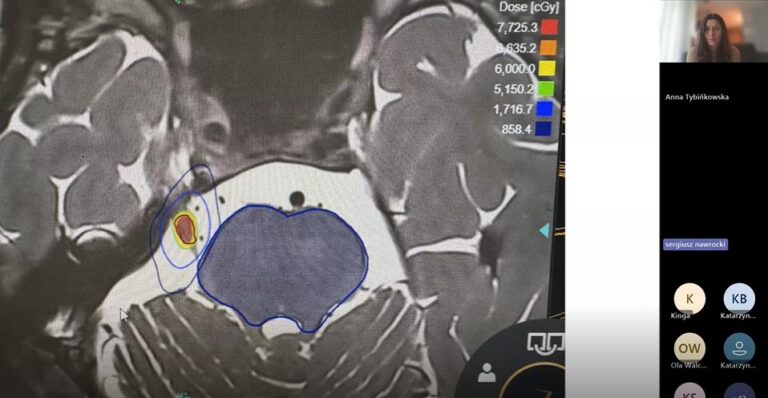

- unikalne cechy systemu ZAP-X, który pozwala na precyzyjne leczenie zmian nowotworowych bez konieczności użycia klasycznego akceleratora,